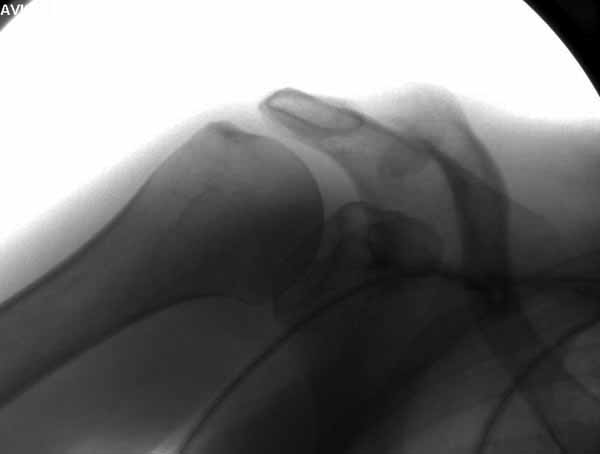

Re: ключичная пластинка

Отправитель: Серж 24 Июнь 2011, 13:42

|

foto 3

3.JPG

14KB (15209 bytes)

Отправитель: Серж 24 Июнь 2011, 13:43

foto 4

4.JPG

14KB (14434 bytes)

Отправитель: Серж 24 Июнь 2011, 13:45

foto 5

коллаж у меня не получился, пришлось отдельно рентгенограммы присоединить :-))

5.JPG

15KB (16356 bytes)

Мне кажется что если понять принципы, то можно использовать и короткую пластину. Что мы с успехом применяли раньше и применяем сейчас, но уже более осознанно. В вашем случае Серж, у меня стойкое ощущение, что необходима дополнительная иммобилизация, так как неправильно выбрано место введения крючка и при ранней нагрузке пластину просто вырвет. Если вам несложно не могли бы вы продемонстрировать прямую и боковую проекцию и в более хорошем качестве. ИМХО

Теоретически можно использовать и короткую пластину. Но на операции дистальный отломок( акромиальный конец ключицы ) был коротким и оскольчатым, поэтому крючок и использование там блокированных винтов в пластине было очень уместно. Доступ - "сабельный удар". Точка введения крючка - сразу сзади от ключично-акромиального сустава. Если честно - больше внимания уделяли репозиции отломков и адекватному расположению пластины на ключице :-) крючок проверяли на прочность фиксации за акромион и полный объем движений в плечевом суставе. После операции рука на косынке, нагрузку ограничили. Снимки есть в нормальном разрешении, но здесь "размер файла не превышал 75 кб." Если есть необходимость залью в пикассу...